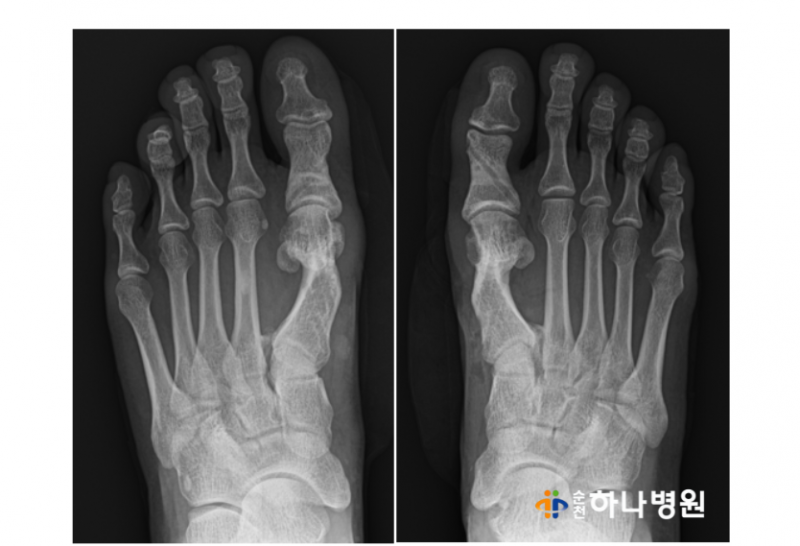

4) 금속나사 제거 수술

특수나사는 굳이 제거하지 않아도 되지만

환자분이 제거를 원할 경우 수술 6개월 후

똑같은 방법으로 제거도 가능합니다.

5) 금속나사 제거 수술 이후 : 바로 일상으로

금속 나사못도 깔끔하게 잘 제거가 됐습니다.

수술 이후 보조기 없이 바로 일상생활이

가능하고 상처 또한 똑같은 미타 방식으로

최소화 되어 나중에 흉터 또한 작습니다.